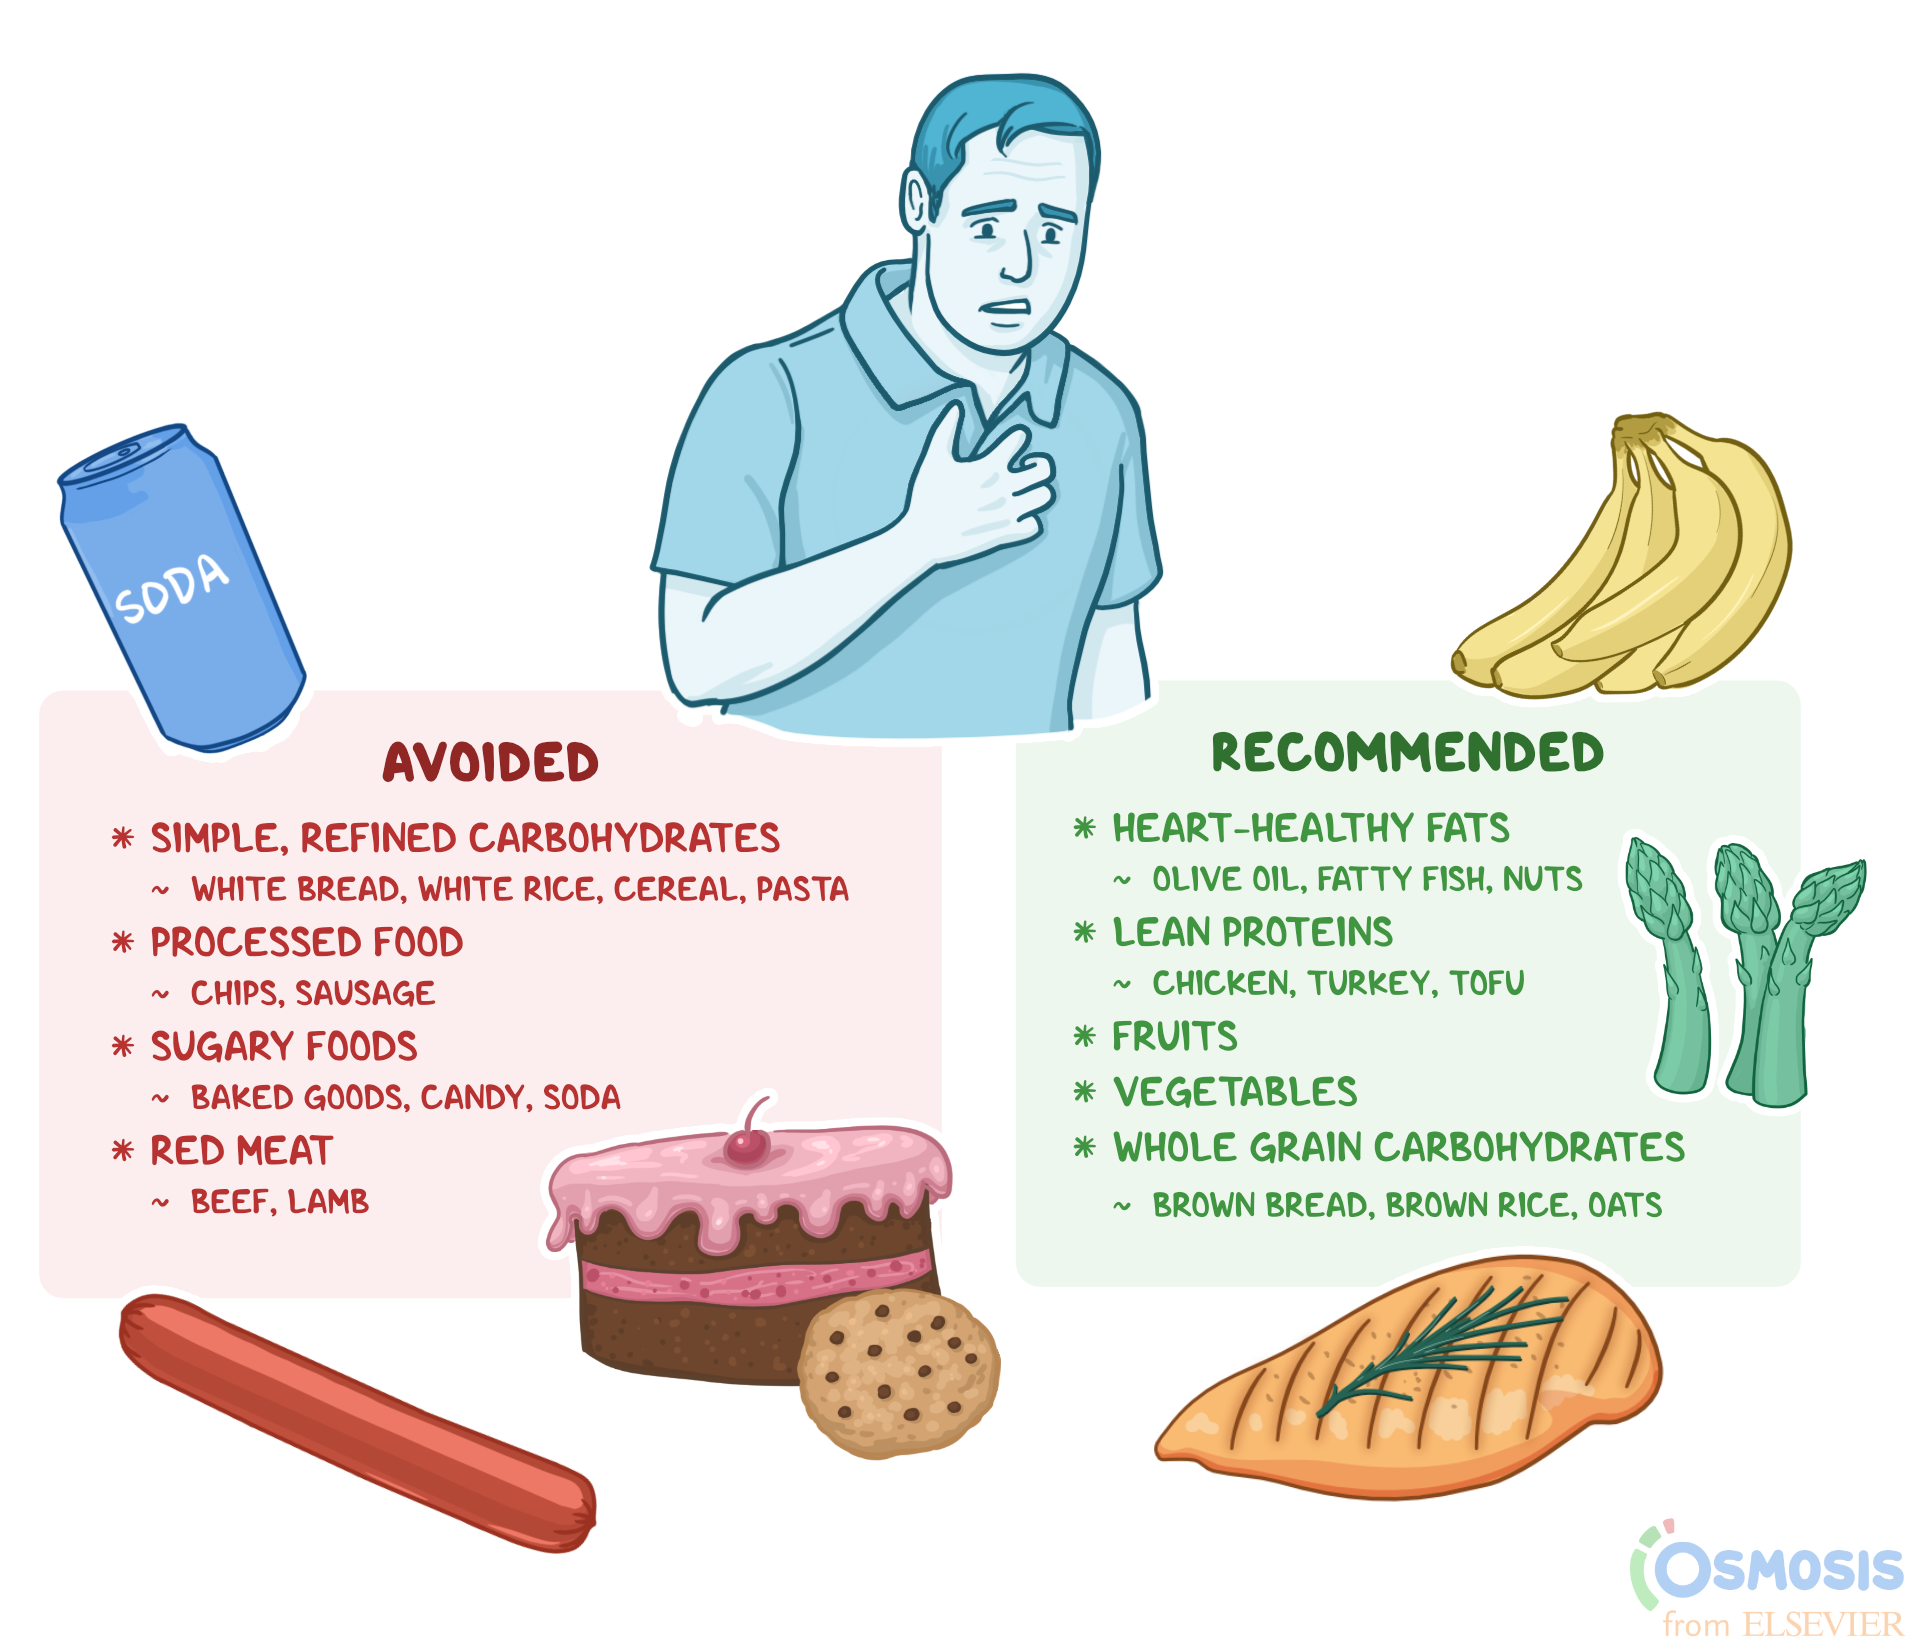

Cardiac Diet What It Is Foods To Consume Foods To Avoid And More

Cardiac Diet What It Is Foods To Consume Foods To Avoid And More

Foods To Avoid With Heart Disease Healthpathy